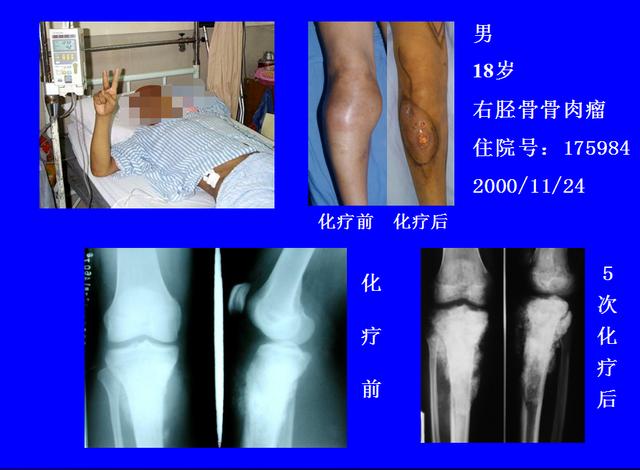

一例胫骨骨肉瘤